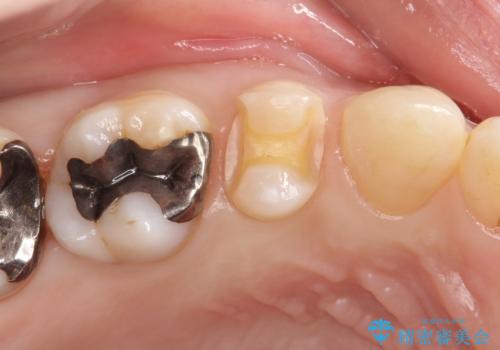

笑ったら銀歯が見える。 セラミックインレーによる治療

- 笑ったときに銀の詰め物が見えることを主訴に来院されました。

セラミックインレーにて修復を行いました。

保険治療で使える材料には制限があり、見た目だけでなく精度でも劣ります。当院でのセラミックインレーは歯とのつなぎ目を拡大鏡で確認して精度高く仕上げるため、むし歯のリスクを限りなく少なくできるよう治療します。